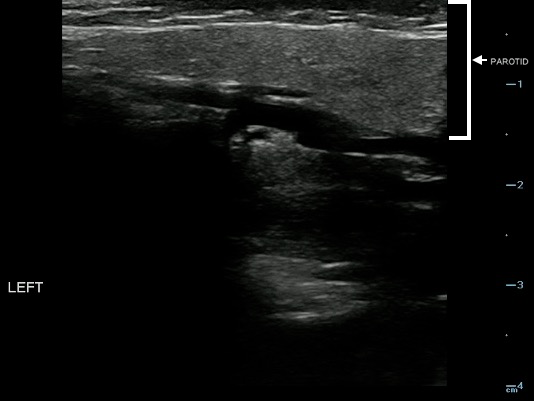

- Figure 18. Normal parotid gland (marked with arrow)

Video 12. Normal parotid gland

- Sonographically, the normal parotid and submandibular glands appear homogeneous; the fatty glandular tissue composition causes an increased echogenicity relative to adjacent muscle.

- Parotid Gland:

- The homogeneity and echogenicity of the parotid gland is comparable to that of the thyroid gland.

- Normal intraglandular salivary ducts and the Stensen’s duct are generally not visualized with ultrasound.

- Parotid short axis should be less than 5– 6 mm normally.13